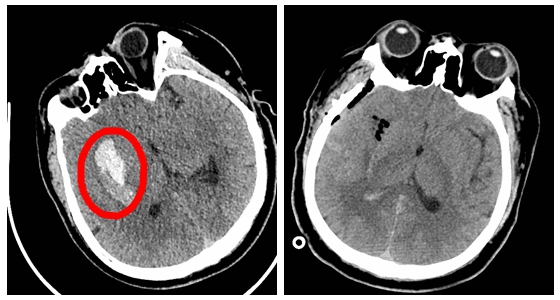

1月28日,除夕夜, 万家灯火,阖家团圆之夜,湘雅常德医院的医护人员为了病人的健康和安危,舍小家为大家,坚守在工作岗位上,用辛劳的汗水无私地奉献在救死扶伤的第一线。晚上7:00,常德...